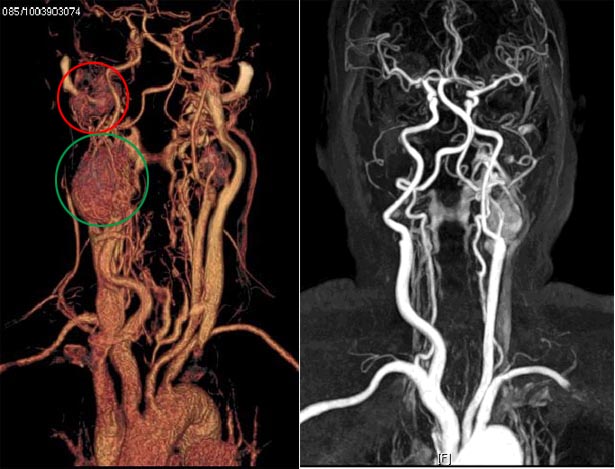

左图为术前重建图,红圈处是右侧颈静脉体瘤,绿圈处是右侧颈动脉体瘤

右图术后重建图显示,右侧的动脉、静脉体瘤被切除干净